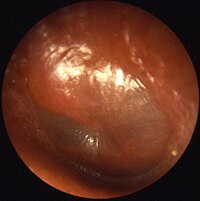

| Acute otitis media (OM)[7] |

317 million worldwide (2017)[8] Affects 80% of children by age 5 years.[9] Most common reason for antibiotic use in young children.[9] |

Typically young children with ear pain (one or both).[8]

Pulling ear, irritability, headache, fever (in 2/3), vomiting,[7] discharge.[8] Bulging red tympanic membrane.[8] +/- Viral upper respiratory tract infection.[7] |

Diagnosis using otoscope.[7]

|

Mostly viral and resolve without treatment, particularly in high income countries.[10]

Antipyretics; (paracetamol, ibuprofen).[8] No ibuprofen if younger than 3-months[8] Prevention: hand hygiene, pneumococcal vaccine, flu vaccine, Hib vaccine[8] |

For severe symptoms, weak immune system, fever ≥39.0 °C, bilateral OM in children younger than 2 years.[8] | |